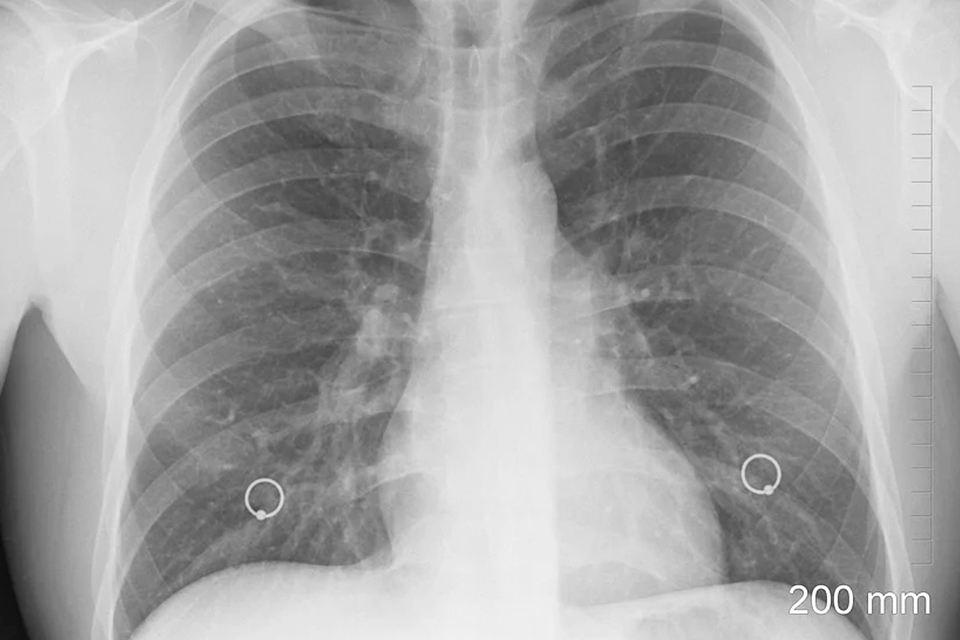

「肺癌」成台灣新國病女性罹患率呈年輕化趨勢 別忽視咳嗽、咳痰、胸痛等警訊以免錯失治療先機

根據國健署癌症登記報告分析,台灣肺癌發生率不斷翻倍成長,近40年間(自1980年至2018年),肺癌發生率增加2.6倍,而女性肺癌發生率則增加4.3倍之多,高於男性2.19倍。